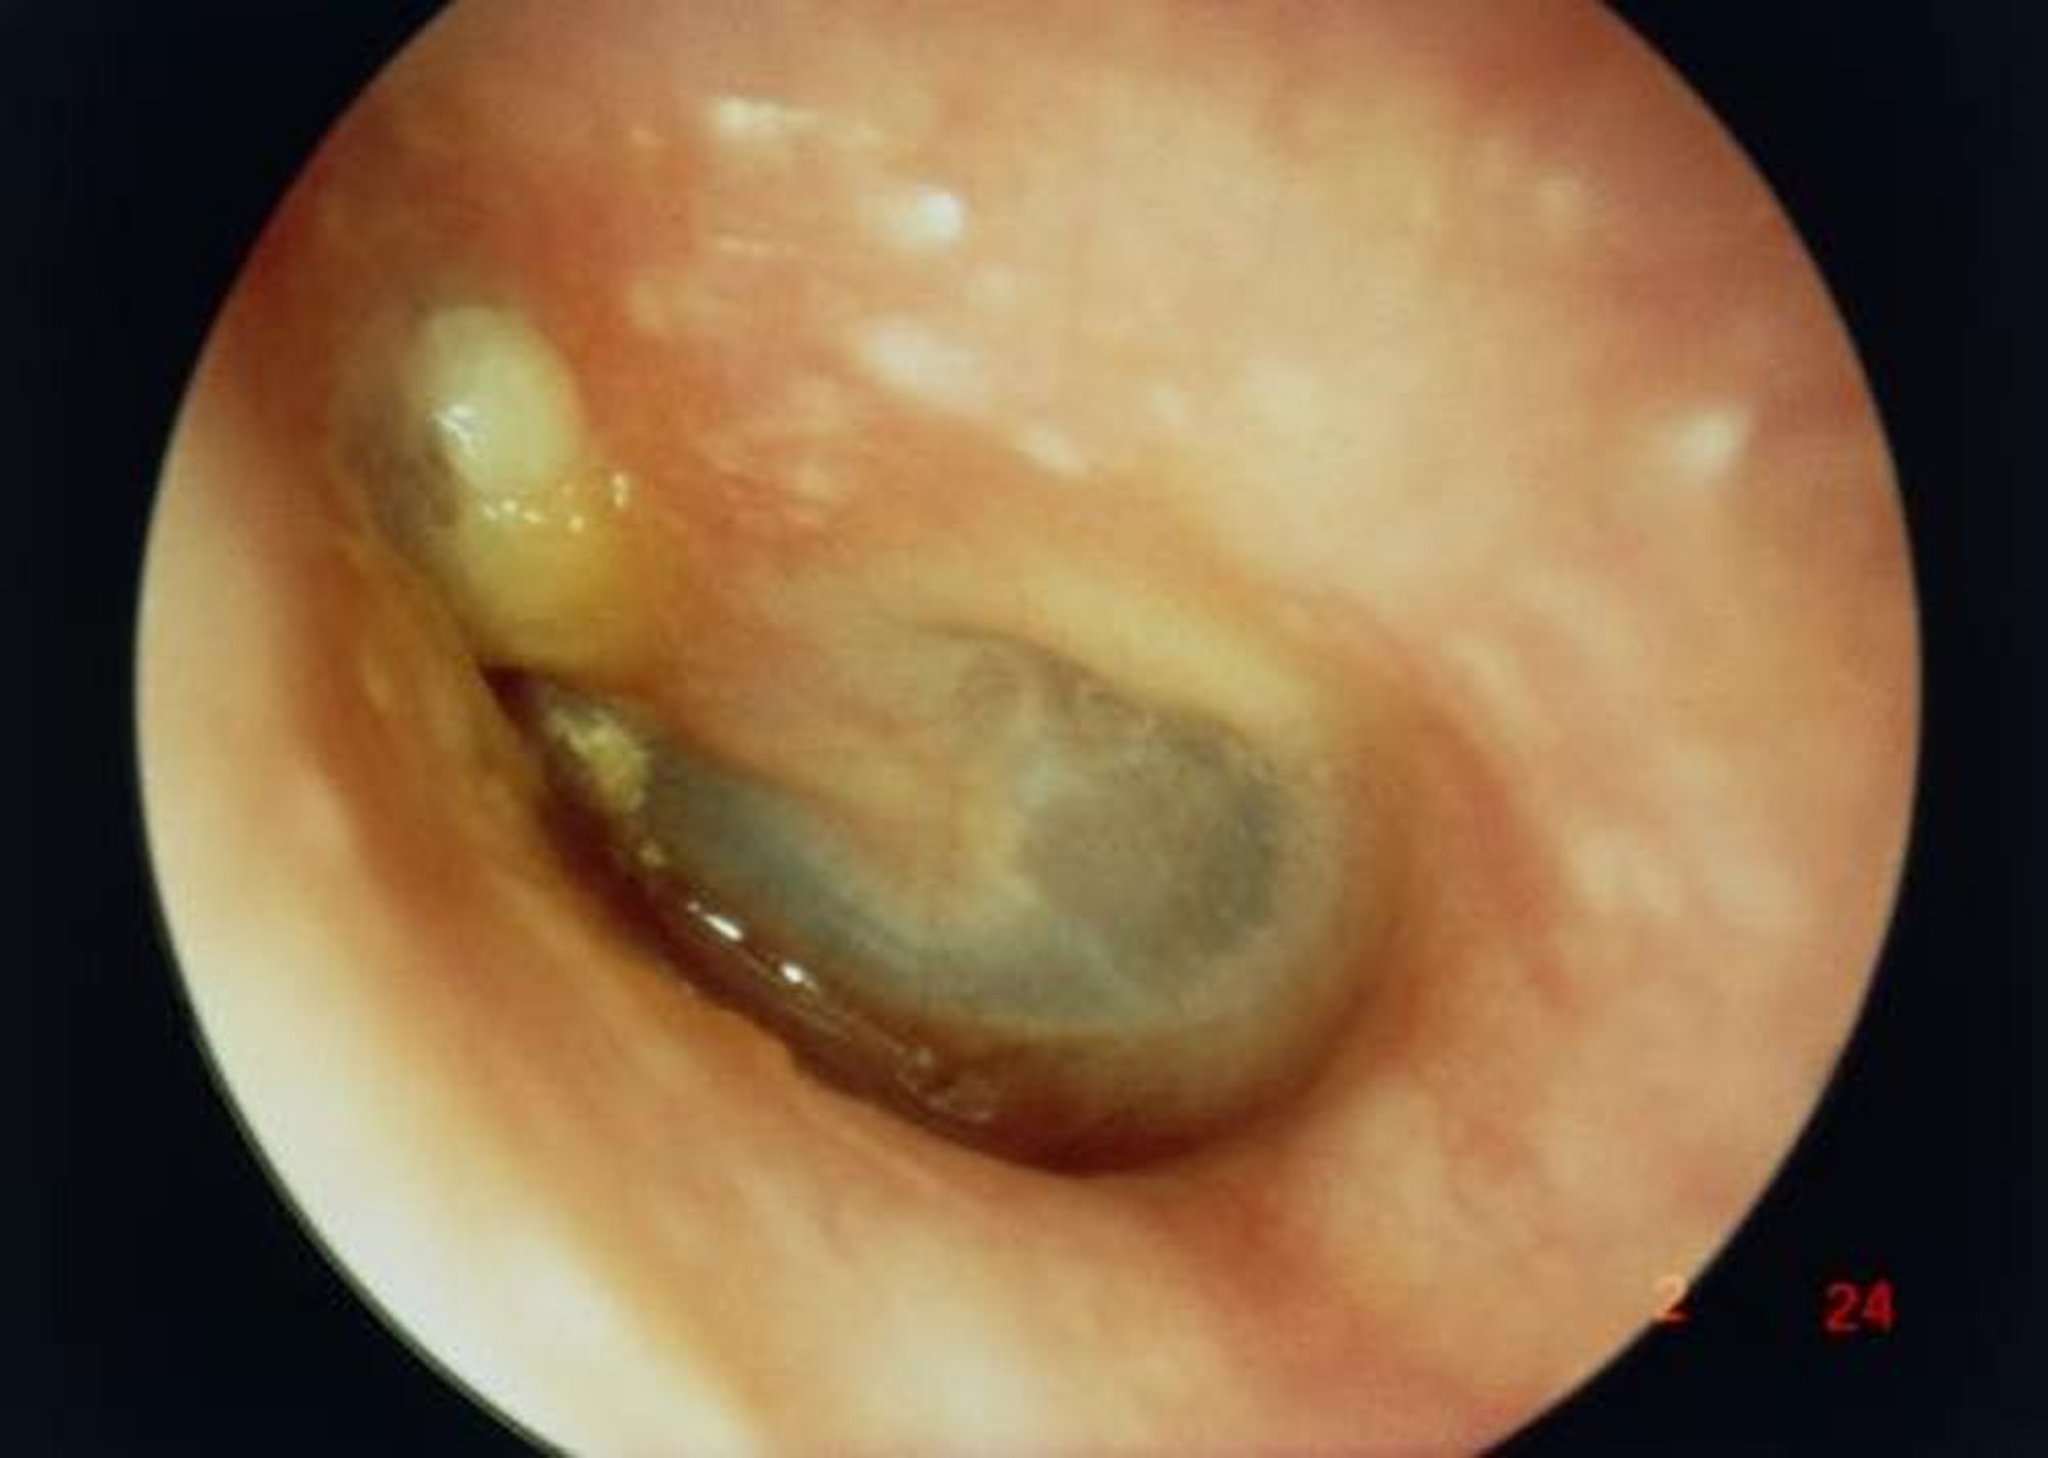

In questa immagine, la vista lungo il canale uditivo esterno mostra un colesteatoma di grandi dimensioni (massa bianca a sinistra superiore al breve processo del malleo) con conseguente perforazione della membrana timpanica.

PROFESSOR TONY WRIGHT, INSTITUTE OF LARYNGOLOGY & OTOLOGY/SCIENCE PHOTO LIBRARY